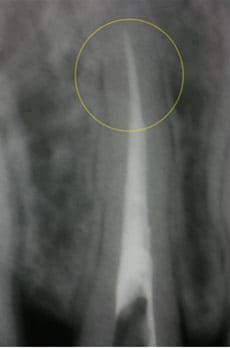

CASE06 マイクロエンド+歯根周囲掻爬(歯周外科)

歯ぐきがよく腫れる主訴で来院。レントゲン写真の術前を見ると大きな影が確認できます。この部分に嚢胞(のうほう)がある状態です。マイクロエンドと歯根周囲掻爬(歯周外科)をすることで改善したケースです。

主訴:歯ぐきがよく腫れる(10代女性)

回数期間:7回 約1年半

治療法:マイクロエンド、歯根周囲掻爬(歯周外科)

治療費用:約35万円(税抜)